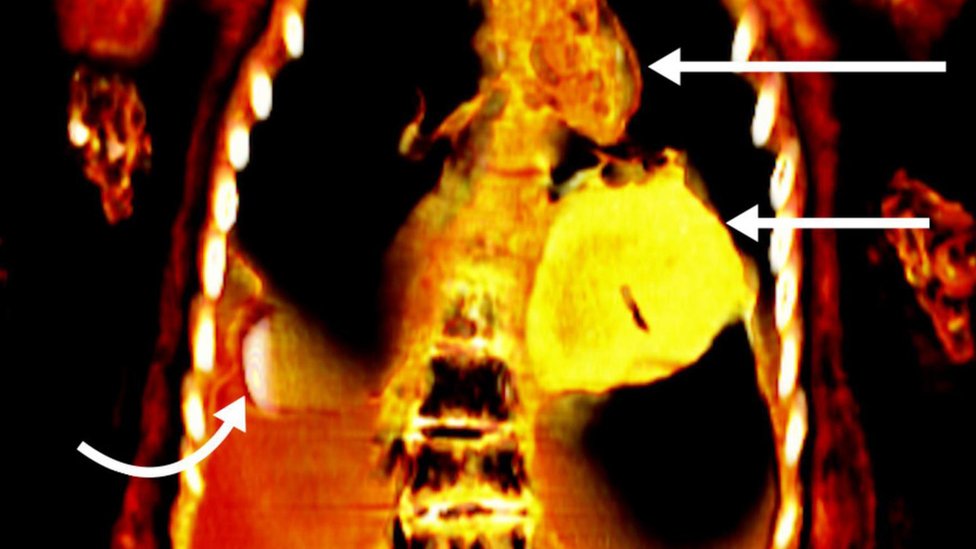

Snimci su pokazali da je telo pokojnika sadržalo 49 amuleta 21 različitog dizajna, a mnogi od njih bili su načinjeni od zlata.

Skenovi su pokazali da se ispod zavoja koji su prekrivali mladićevo telo nalazio dva prsta dugi predmet pored njegovog neobrezanog penisa.

Pokojnik je još imao i zlatni jezik u ustima, kao i skarabej u obliku srca, takođe od zlata, postavljen u grudnom košu.

Danas je upotreba kompjuterizovane tomografije postala sjajno oruđe za proučavanje ostataka bez njihovog oštećivanja, što će naučnicima omogućiti da otkriju više o „zdravlju, verovanjima i sposobnostima ljudi iz drevnih vremena“, kaže ovaj stručnjak.

„Kompjuterizovana tomografija predstavlja značajan napredak u radiologiji.

„Umesto da se koristi samo jedan snimak, hiljade projekcija tankih delova (isečaka) tela mogu se kombinovati u potpuni trodimenzionalni model“, zaključuje on.